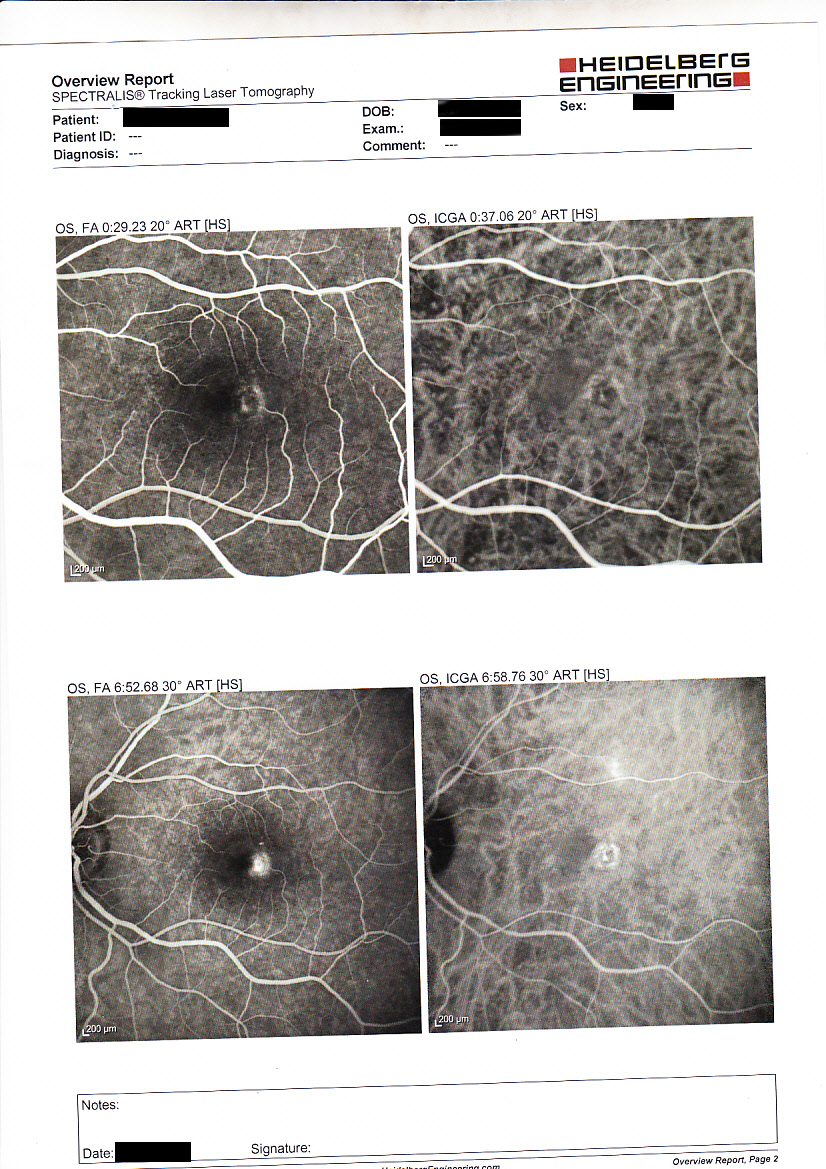

2 Teleangectasie Retiniche Iuxtafoveali Idiopatiche tipo 1B

Paziente di 55 anni riferisce "disturbi del visus" non meglio specificati nell'occhio sinistro il visus era di 9-10/10 nmcl e il quadro oftalmoscopico era suggestivo di teleangectasie, effettuati OCT e fluorangiografia (vedi esami allegati), è stata posta diagnosi di Teleangectasie Retiniche Iuxtafoveali Idiopatiche tipo 1B ed è stato programmato il follow up indicato.

A distanza di 5 anni il quadro clinico è rimasto invariato.

OCT: confermato distacco sieroso occhio sinistro (vedi allegato)

Fluorangiografia (FAG): evidenziata membrana neovascolare (CNV) (vedi allegato)